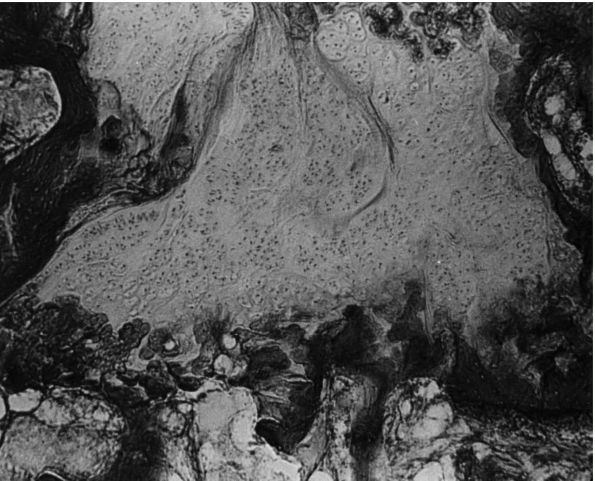

cartilage of patients with LCPD were described as early as 1913 by

Perthes. The superficial zone of the cartilage covering the affected

femoral head is normal but thickened (Figure 15-13).

In the middle layer of the epiphyseal cartilage, however, two types of

abnormalities are seen: areas of extreme hypercellularity, with the

cells varying in size and shape and often arranged in clusters; and in

other areas, a loose, fibrocartilaginous-like matrix. These abnormal

areas in the epiphyseal cartilage have different histochemical and

ultrastructural properties than normal cartilage or fibrocartilage.

Areas of small secondary ossification centers are evident, with bony

trabeculae of uneven thickness forming directly on the abnormal

cartilage matrix.

![]() |

|

FIGURE 15-13. Anatomic regions of the proximal femur in a growing child. (Weinstein SL. Legg-Calvé-Perthes disease. In: Morrissy RT, Weinstein SL, eds. Lovell and Winter’s Pediatric Orthopaedics, 5th Ed. Philadelphia: Lippincott Williams & Wilkins, 2001:962)

formation with amorphous debris and extravasation of blood. In the

metaphyseal region, enchondral ossification is normal in some areas;

but in other areas, the proliferating cells are separated by a

fibrillated cartilaginous matrix that does not calcify. The cells in

these areas do not degenerate but continue to proliferate without

enchondral ossification. This is evidenced by “tongues” of cartilage

extending into the metaphysis as bone growth proceeds in adjoining

areas (Figure 15-14).

FIGURE 15-14.

Photomicrograph (×80) showing a large area of cartilage in between the bone trabeculae of the femoral neck (case 1). (Ponseti IV. Legg-Perthes disease: observations on pathological changes in two cases. J Bone Joint Surg 1956;38A:739) |